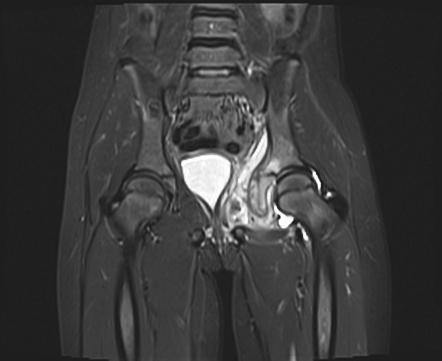

Компьютерная томография более информативна и позволяет детально оценить структуру кости, выявить секвестры и внутрикостные полости.

считается «золотым стандартом» ранней диагностики, так как позволяет выявить воспаление костного мозга, мягких тканей и суставов на ранних стадиях.